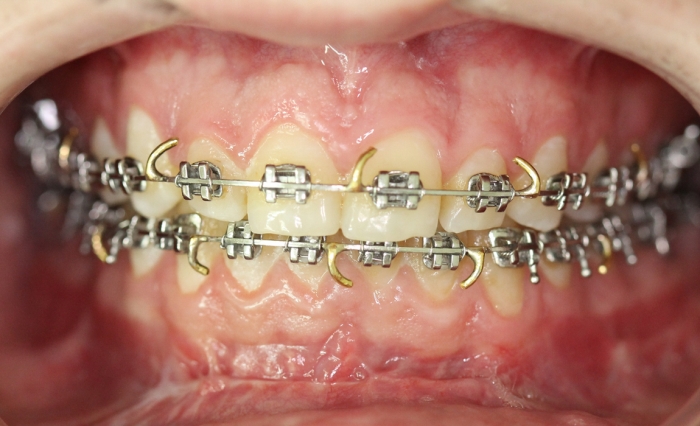

Mordida após a cirurgia